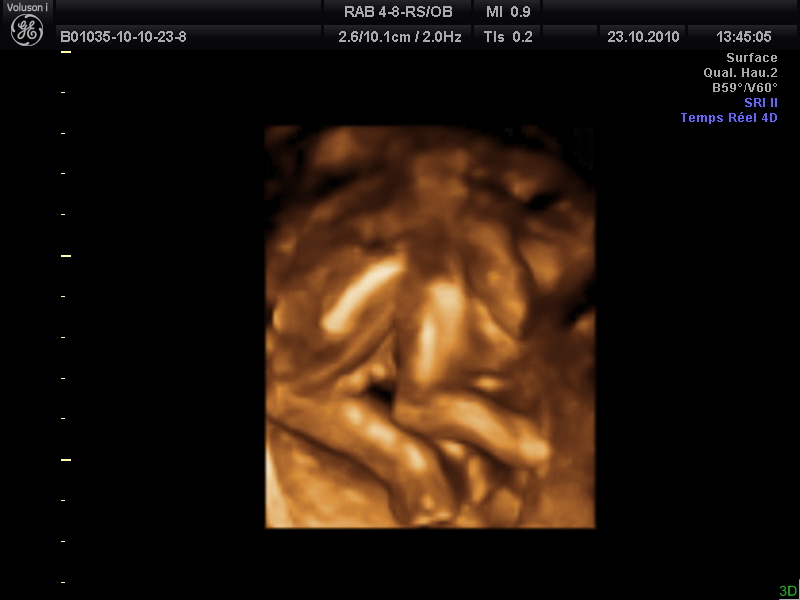

Echographie 2ème trimestre bourses? L'échographie 4D permet d'évaluer avec précision la morphologie exacte du fœtus et de l'environnement fœtal (placenta, liquide amniotique, cordon ombilical), l'aspect hémodynamique du fœtus avec le mode DopplerCoupleur et donc une appréciation avec preuve de la vitalité dudit fœtus B L'échographe Voluson 730 permet deFille ou garçon le choix de savoir C'est au cours de l'échographie du 5 ème mois que l'échographiste est en mesure d'annoncer aux futurs parents le sexe de leur enfant de façon fiable La détermination est parfois possible dès le 3ème mois

Echographie 4d 5d Dexeus Mujer